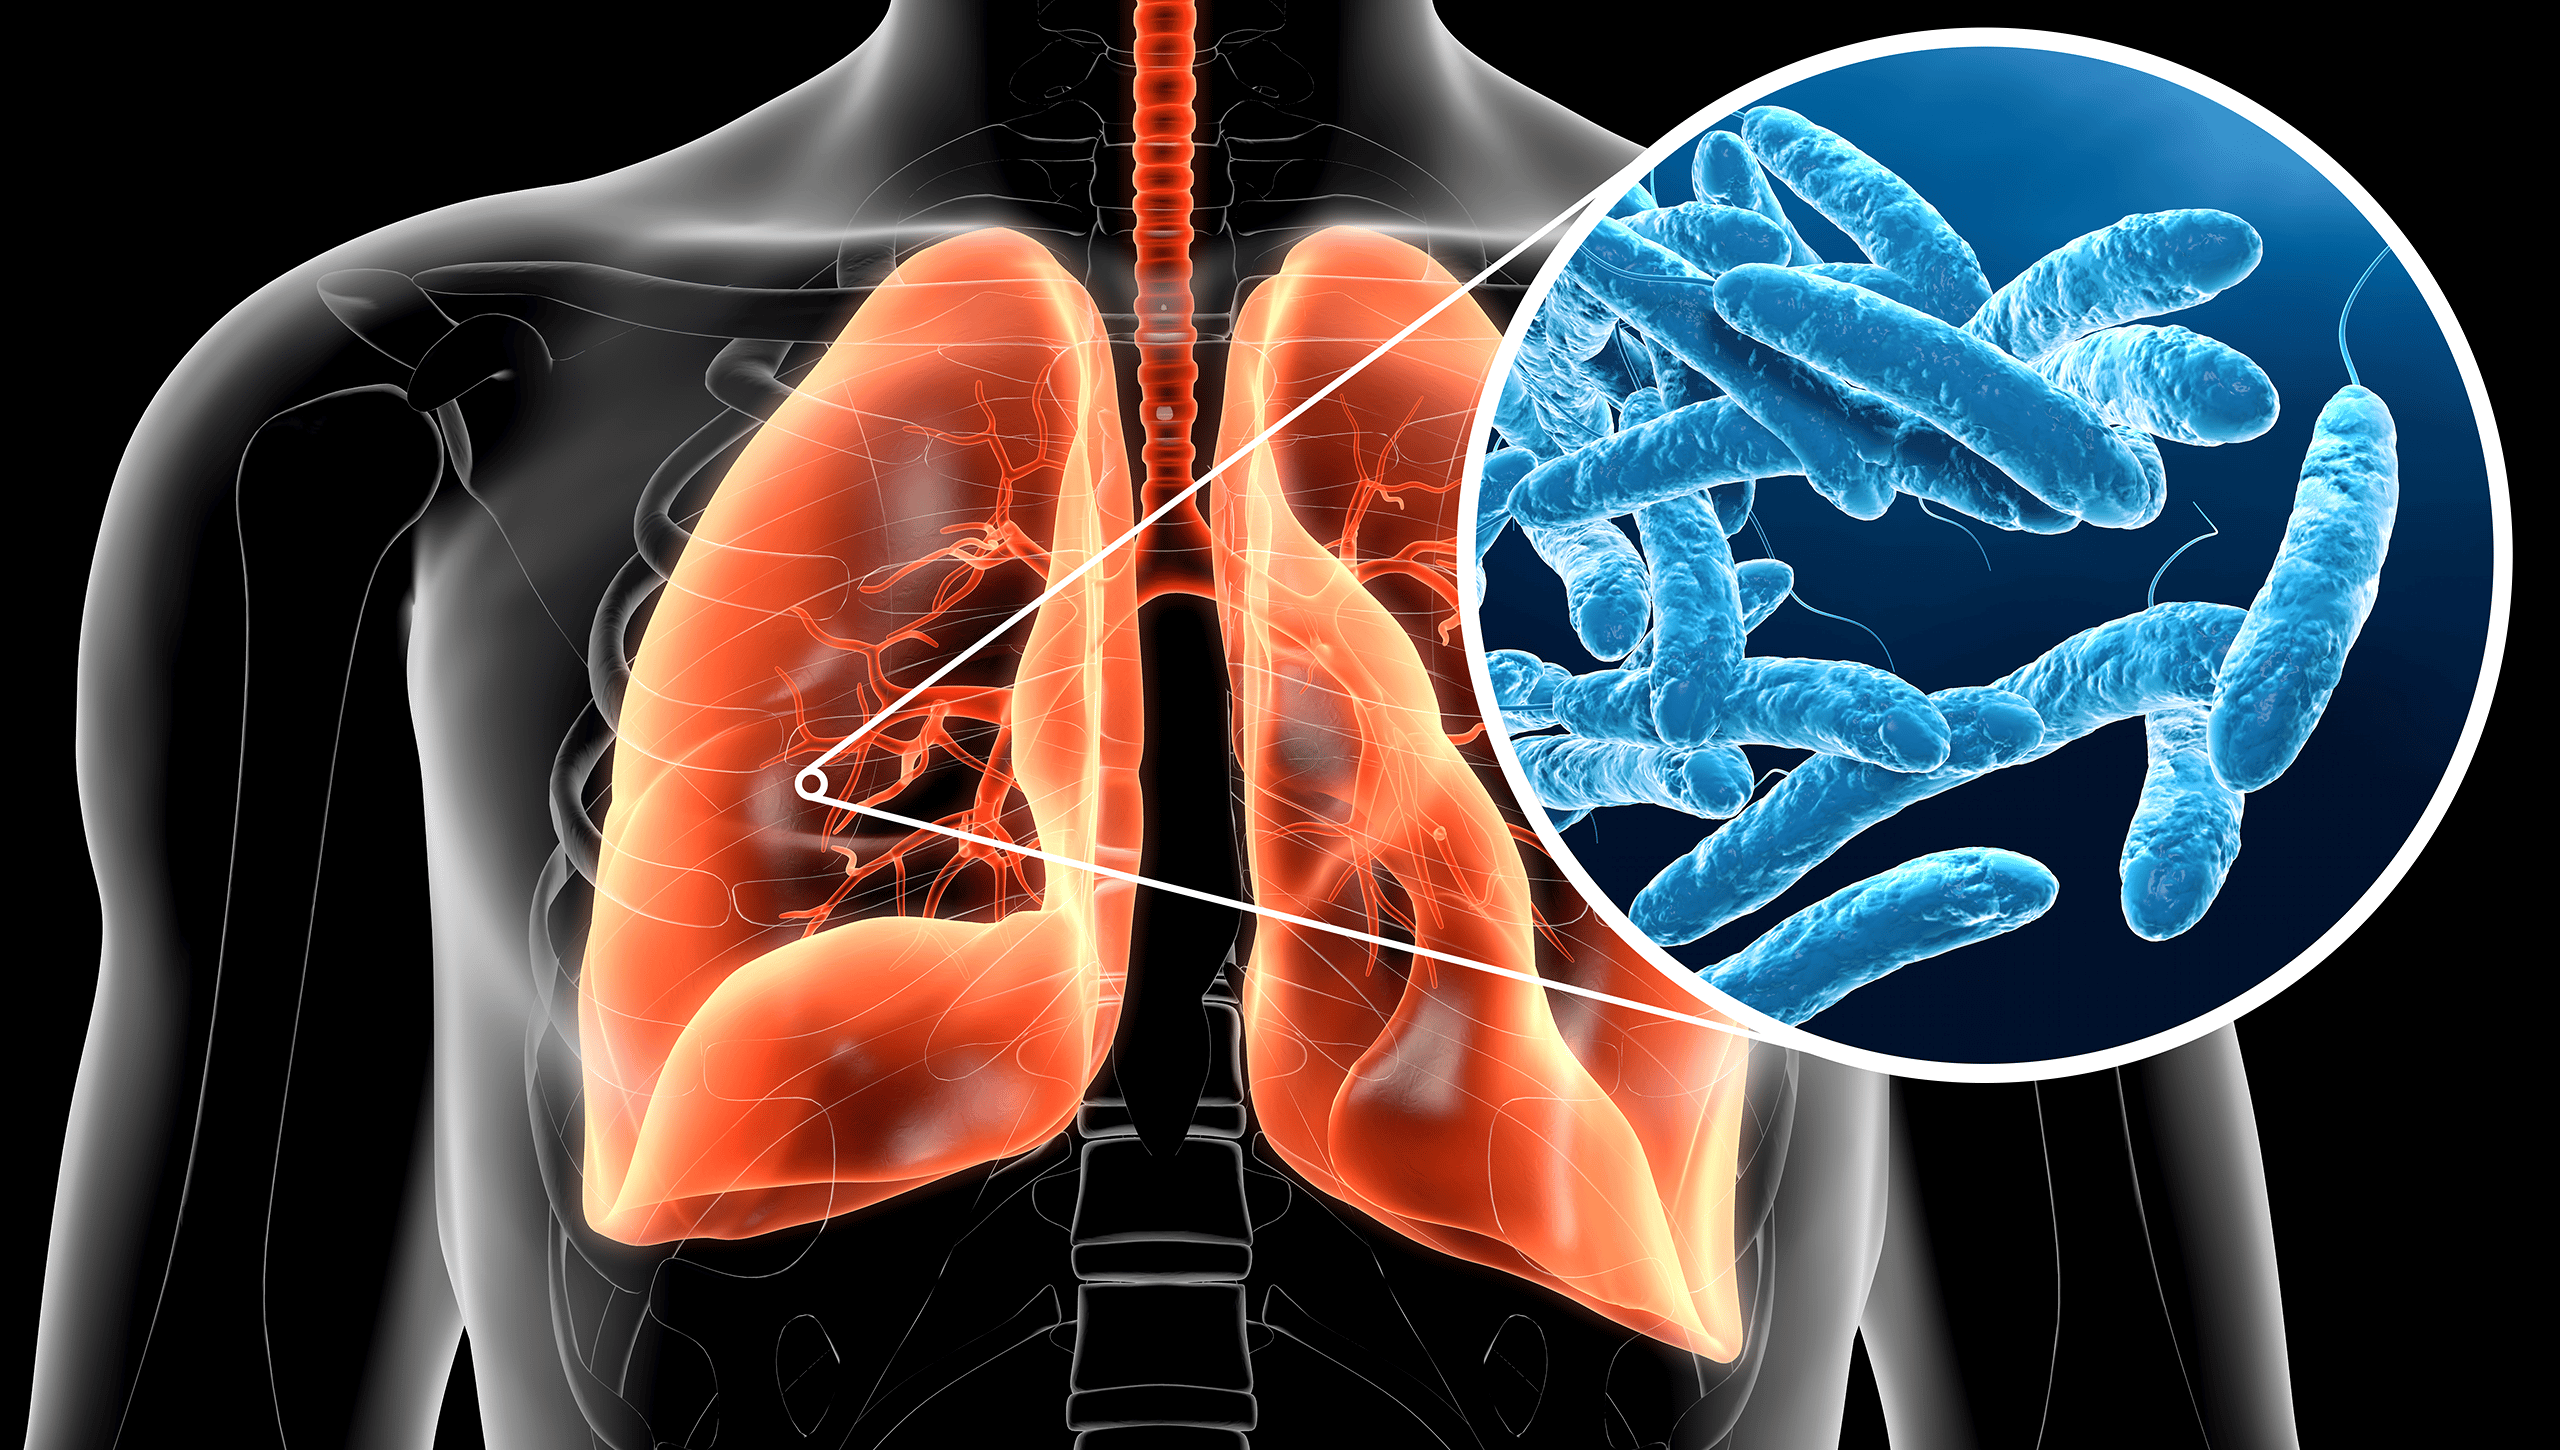

FABRICA DI ROMA – Purtroppo, l’amministrazione di Fabrica di Roma ha da poco fatto dietrofront sulle ultime dichiarazioni che andavano a smentire il sindaco di Civita Castellana in merito a un caso di legionella segnalato anche nel territorio di Fabrica.

Come esplicitato dal Comune: “A rettifica della precedente comunicazione, vi informiamo che a seguito di ulteriori verifiche nella ricezione delle comunicazioni pec, abbiamo appurato che un caso di positività al batterio della legionella di un nostro concittadino, ci era stato segnalato, per conoscenza, dalla ASL Viterbo in data 11/7/2024”.

Il cittadino in questione, fortunatamente, sarebbe però ora fuori pericolo.

In ogni caso, l’amministrazione tiene a sottolineare che “Confermiamo la restante parte della comunicazione e di aver richiesto alla Talete un sollecito monitoraggio sulla rete idrica comunale, i cui esiti ci saranno comunicati secondo i tempi tecnici indicati. Esprimiamo al nostro concittadino e ai suoi familiari il seppur tardivo compiacimento per aver positivamente superato la fase più critica della patologia”.